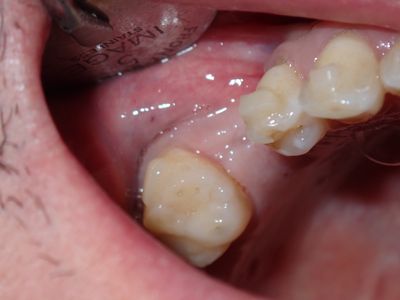

Bilateral sinus augmentation done in 2023, no significant findings at time of surgery nor post op. Post panorex shows good location of bone. Complete loss of graft material. Will try internal and use prf sticky bone using only cortical and xenograft this time. Osteotomy prepared to about 2mm, remainder with densah drills to expand limited B-L width of bone. entry into sinus chamber with CAS-kit drills, no evidence of membrane perforation, packed about .5 cc of bone, good pushback of bone, implant placed, buccal region grafted with the same sticky bone folloewd by collagen membrane with hole cut for implant, healing abutment placed, prf fibrin membrane over crest